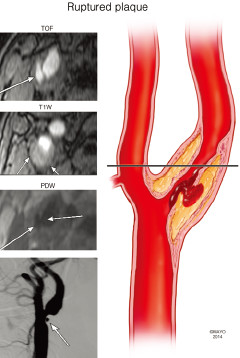

讨论:狭窄率一样,治疗方法就一样吗?

题目:四个患者ABCD去医院体检,都做了超声,发现有颈动脉斑块,且管腔狭窄率基本一样(60%左右),后续又安排做了高分辨核磁,发现A的斑块以钙化为主,B以大脂质核为主,C有斑块内出血,D的斑块已经破裂(如下图所示),ABCD都尚未出现脑缺血症状······

C

3.jpg